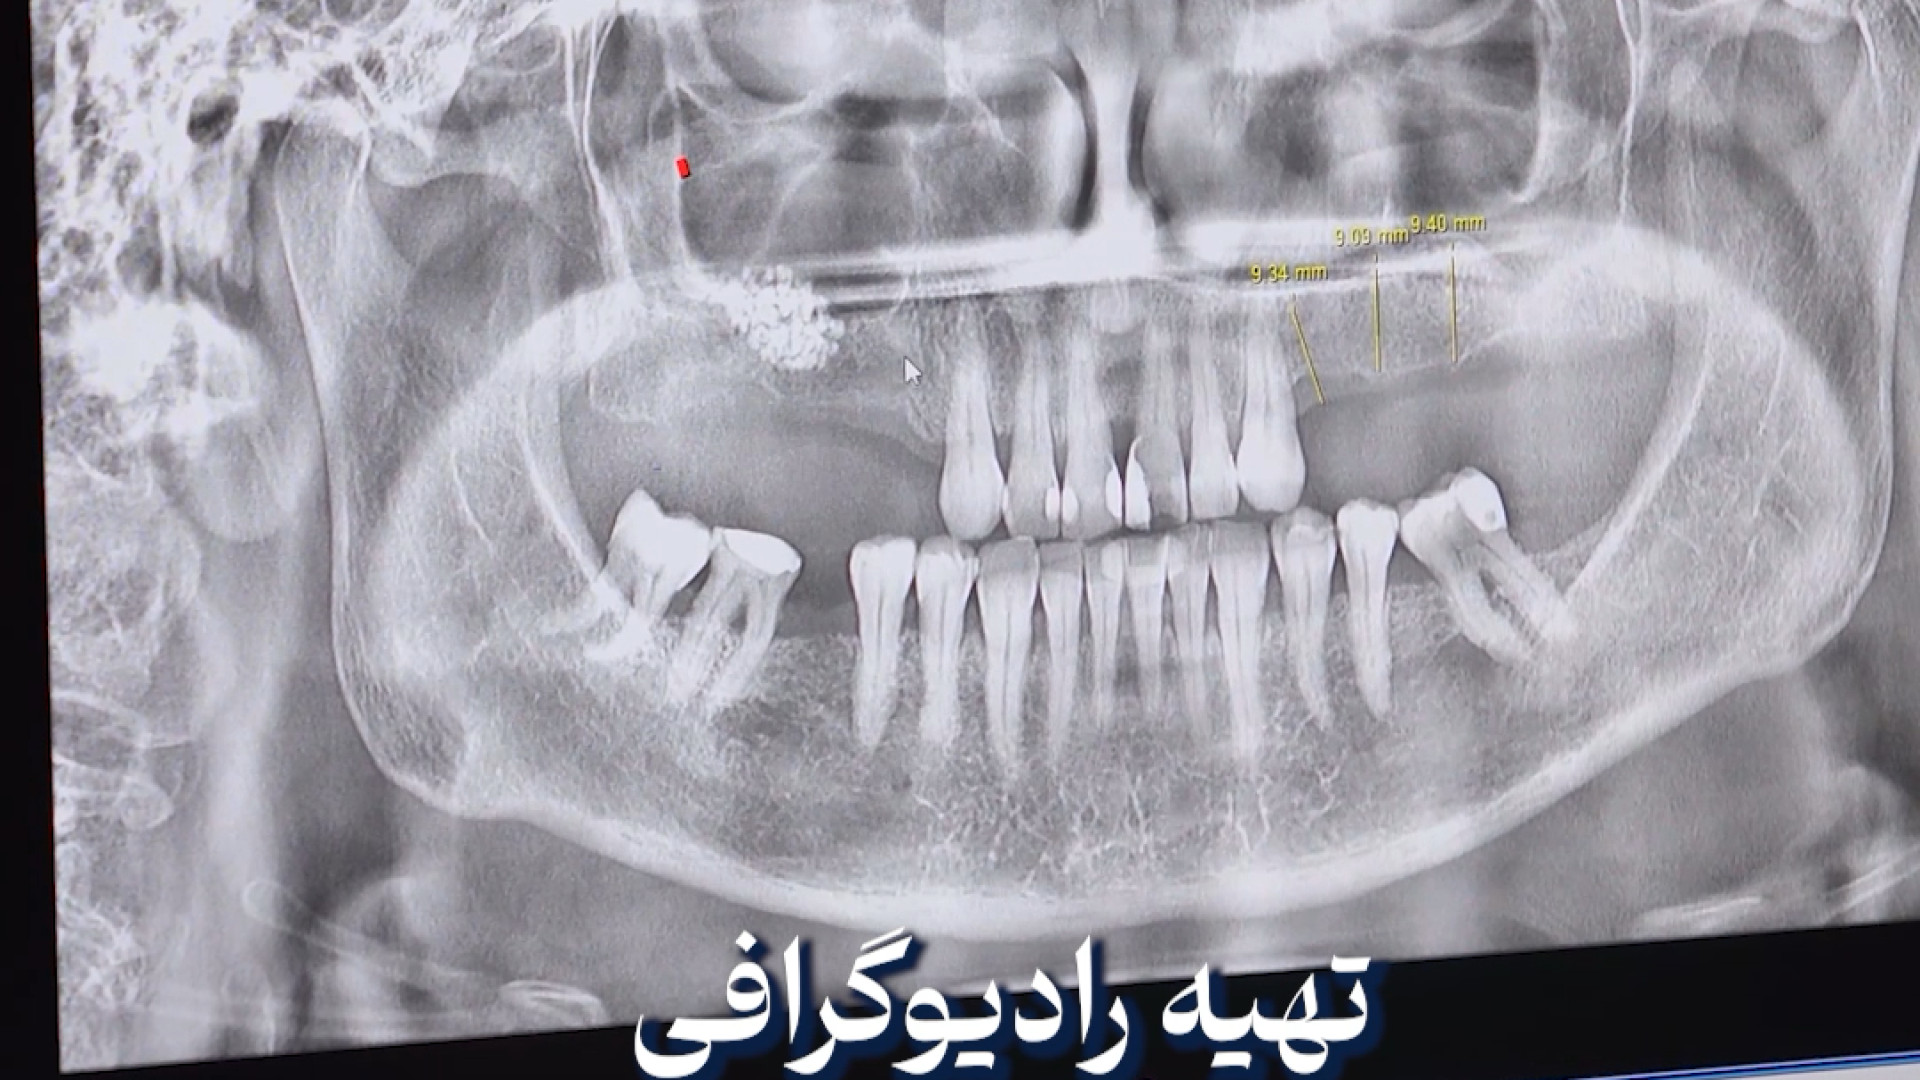

نکاتی که باید قبل از شروع ارتودنسی رعایت کنید. بازدید : 1 0 لایک دکتر علیرضا خدیوی منتشر شده در تاریخ 10 دی 1404 15:41 ارتودنسی,متخصص ارتودنسی,بهترین متخصص ارتودنسی,دکتر ارتودنسی,ارتودنسی دندان ادامه سلامت و تندرستی